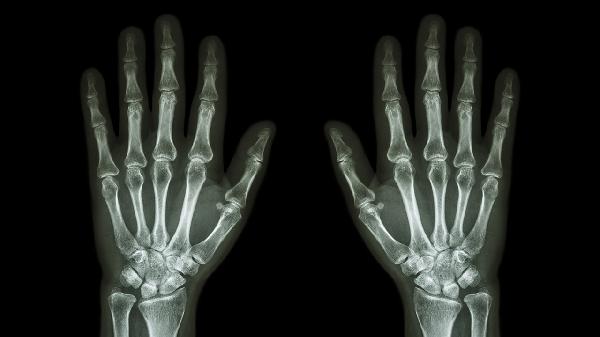

怎么护理手指关节肿大疼痛患者

手指关节肿大疼痛可通过热敷冷敷、药物治疗、关节保护、适度运动、营养补充等方式护理。关节肿痛通常由骨关节炎、类风湿关节炎、外伤、痛风性关节炎、感染性关节炎等原因引起。